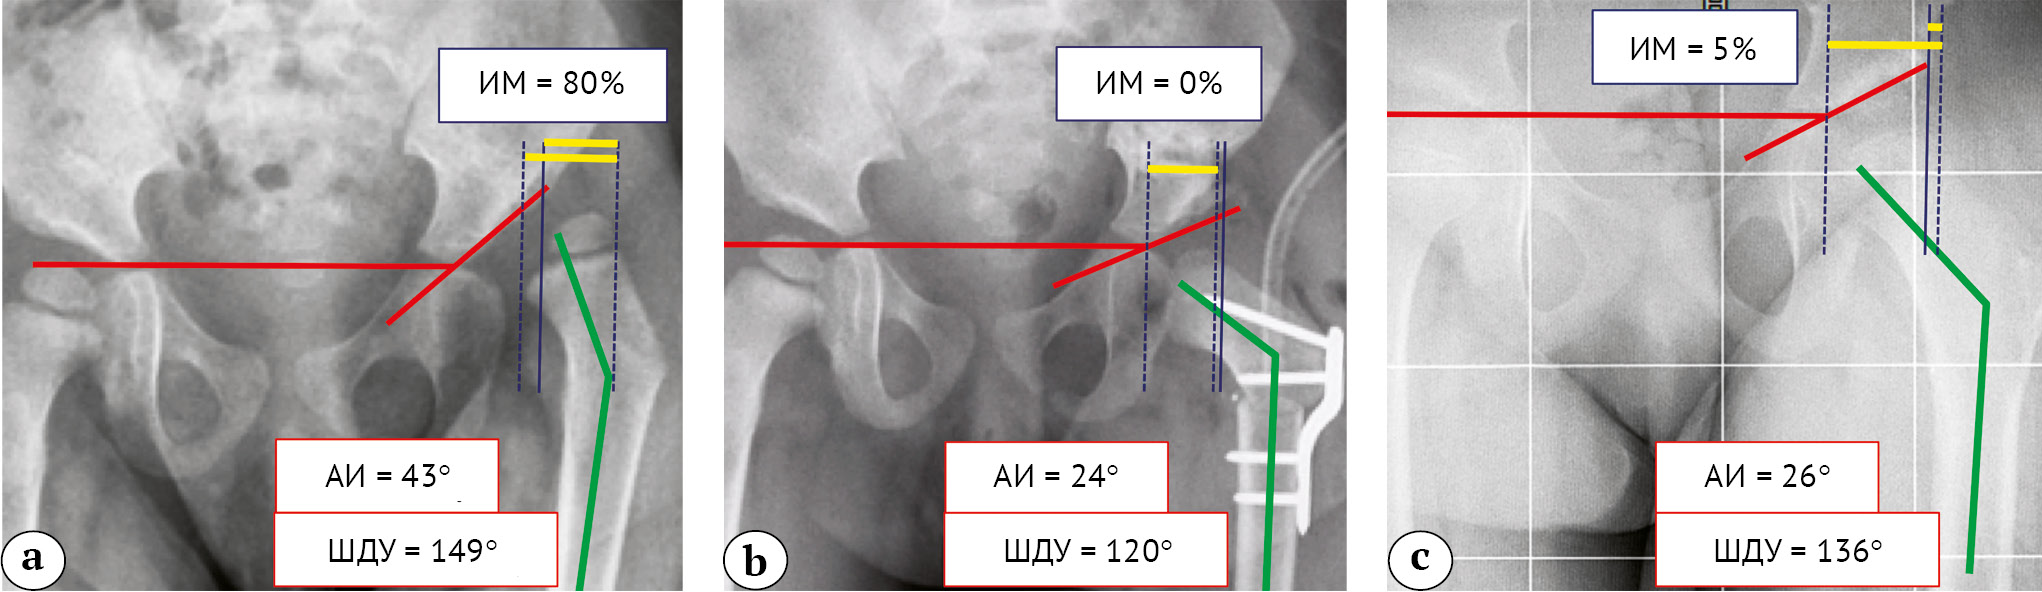

Средний срок наблюдения составил 31,9±4,9 мес. (от 12 до 66 мес.). Для оценки проведенной коррекции выполнен сравнительный анализ рентгенограмм: ацетабулярный индекс (АИ), шеечнодиафизарный угол (ШДУ) и индекс миграции Реймера (ИМ)) до (АИ1, ШДУ1, ИМ1), после операции (АИ2, ШДУ2, ИМ2) и на последнем осмотре (АИ3, ШДУ3, ИМ3). Проведена оценка частоты возникновения осложнений: рецидив вывиха, АНГБК, несращения, инфекция и потеря коррекции. У 8 пациентов с периодом наблюдения более 2 лет проведена оценка разницы длины конечностей (рис. 2).

Рис. 2. Рентгенометрические параметры таза пациента 2 лет 1 мес.: а — до операции; b — после операции; с — на последнем осмотре

Fig. 2. Radiometric parameters of the patient's pelvis aged 2 years and 1 month: a — before surgery; b — after surgery; c — at the latest follow-up